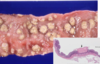

A cat presents to your clinic for drooling, weight loss, and suspected oral pain. The cat is FIV positive and the owner thinks this illness may be related. You sedate the cat for a full oral exam and discover these lesions in her throat. What is the disease?

Feline chronic gingivo-stomatitis (FCGS)